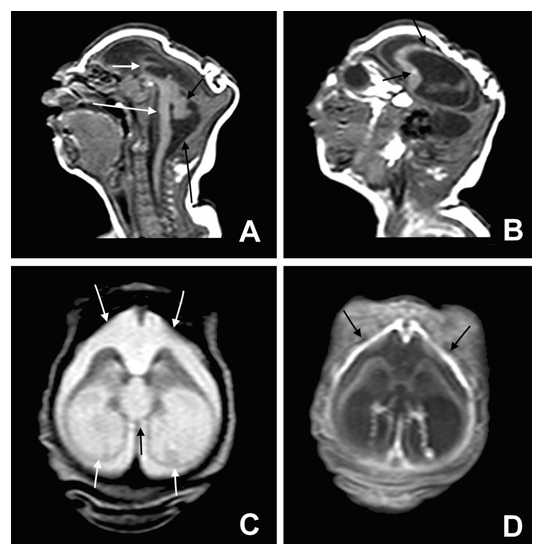

Figura 1. A,B,C,D de microcefalia en Zika. Tomadas de BMJ 2015 http://www.bmj.com/cgi/doi/10.1136/bmj.i1901. Nótese que la microcefalia es grave con gran colapso craneal (B), dato típico de microcefalia por esta entidad